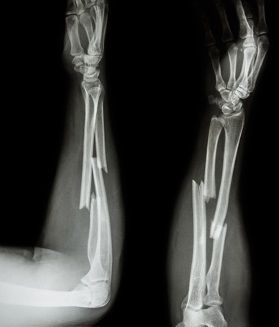

Fracture usually refers to a break in the bone whereas complex fractures are when there is severe damage or break to a bone. This is also known as compound fracture. damage to the soft tissue. Complex fractures are open fractures which in most cases, have the bone protruding out of the socket, through the skin. It also damages the soft tissue, ligaments, joints and tendons. The nature of complex fractures are frail and generally require proper surgical treatment in order to treat and heal the damage. Dr.Praful’s orthopedic clinic offers the best complex fracture surgery in Hyderabad with completely safe and guaranteed results.

Complex fractures, such as multi-fragment, joint-involving, or pelvic fractures, need precise diagnosis and specialized care. At Malakpet, Dr. Praful Kilaru provides advanced imaging, careful surgical planning, and personalized treatment to ensure proper bone alignment, stable healing, and preserved joint function. These fractures often result from accidents, falls, or sports injuries, and his structured, evidence-based approach helps patients regain mobility and return to daily life safely and confidently.

Diagnosis of Complex Fractures

X-rays to identify the Bone fracture

CT scan or MRI for complex injuries

We use digital X-rays, CT scans, MRI scans, and 3D imaging to accurately evaluate fracture patterns and surrounding tissue damage.